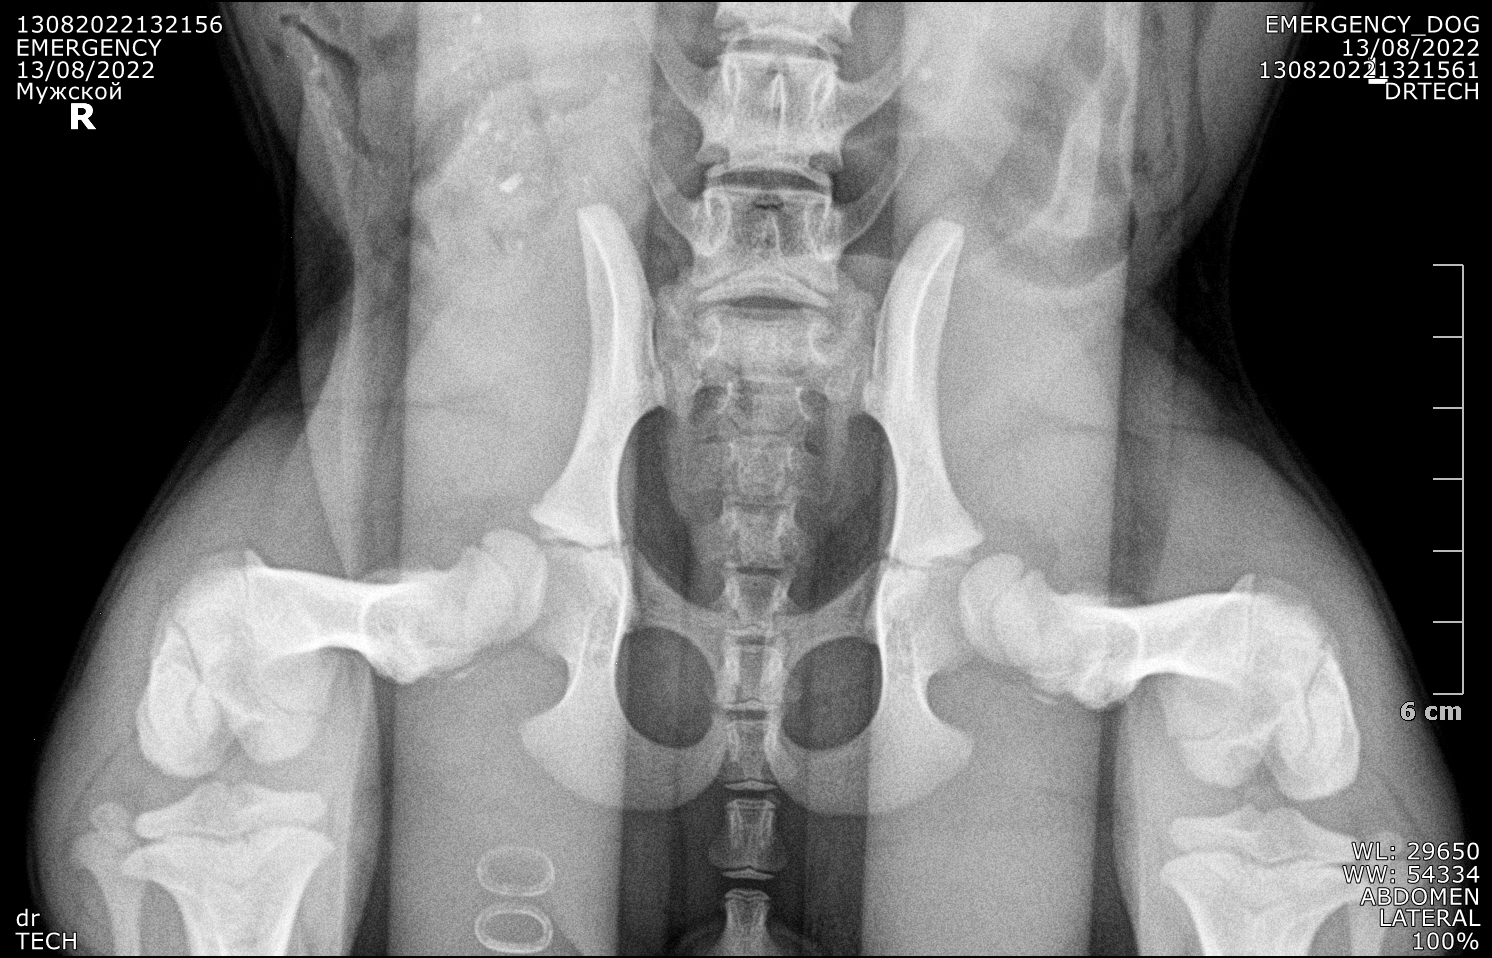

Ещё один снимок суставов (добавил после публикации, в комментах сказали, что по тем снимкам, что я выложил сразу индекс дистракции не определяется):

Друг порекомендовал проверить суставы собаки, что я и сделал. Оказалось, что у собаки индеск дистракции тазобедренных суставова 0.78/0.82 и , потенциально, будет развиваться дисплазия и остеоартроз в тяжёлой форме.